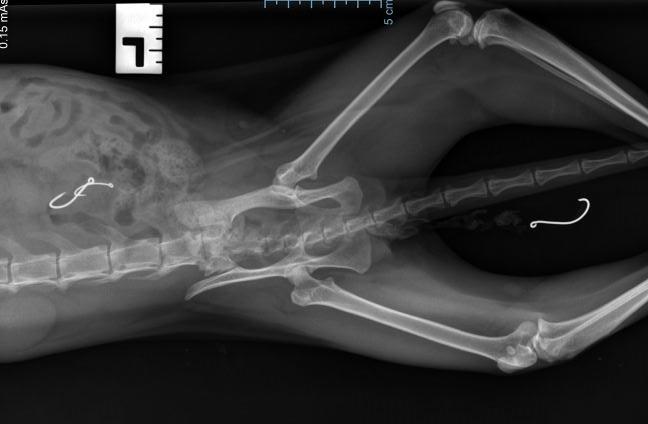

Horrified at realising that poor Sherbet had at some point ingested fishing lines, she was rushed back to the vet. After an X-ray, our team were shocked to see that there were two more fish hooks inside her bowels, with the third still hanging outside of her body with the lines.

Two more fishing hooks were found inside Sherbet's bowels.

The vet scheduled an urgent surgery to remove the hooks and lines.